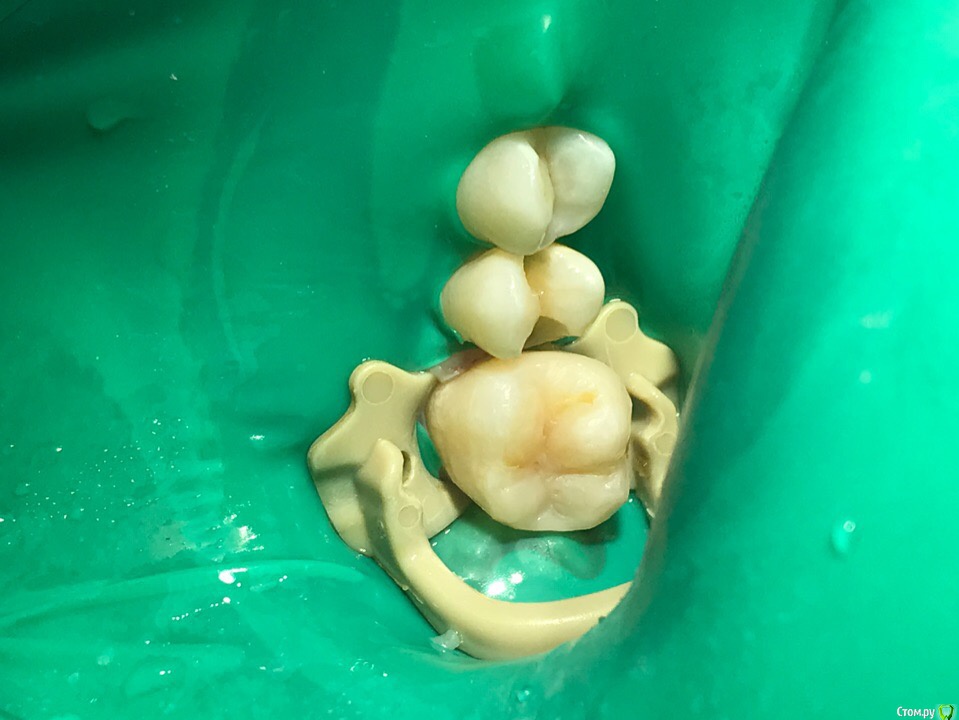

1586Doc Опубликовано 27 июля, 2019 Автор Поделиться Опубликовано 27 июля, 2019 21 реставрация Ссылка на комментарий